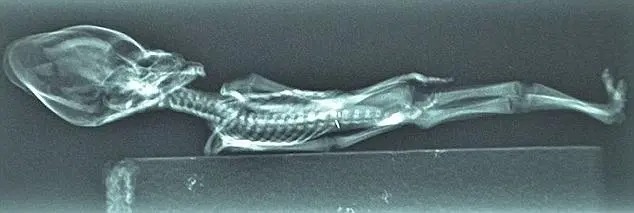

Длинный конусоподобный череп, косые глазницы и меньшее количество ребер, чем в нормального человека, — 10 пар вместо 12-ти – вызвало много невероятных предположений о происхождении останков. Уфологи сразу начали изучать место, где их обнаружили. Некоторые предполагали, что скелет принадлежал инопланетянину или члену особого племени.

В 2018 году группе ученых удалось опровергнуть теории о внеземном происхождении мумии. Результаты исследований, проведенных в лучших университетах Сан-Франциско и Калифорнии, показали, что существо умерло 40 лет назад. Оно страдало от нескольких генетических заболеваний, замедливших его рост. Эксперты обнаружили признаки карликовости и других болезней костей.

Считается, что скелет принадлежит недоношенному ребенку или младенцу женского пола, умершему сразу после рождения. Профессор микробиологии и иммунологии медицинского факультета Стэнфордского университета Гарри Нолан (Garry Nolan) уверен, что исследование останков Аты принесет пользу пациентам. Мумия может дать подсказки, которые помогут людям с генетическими проблемами роста.